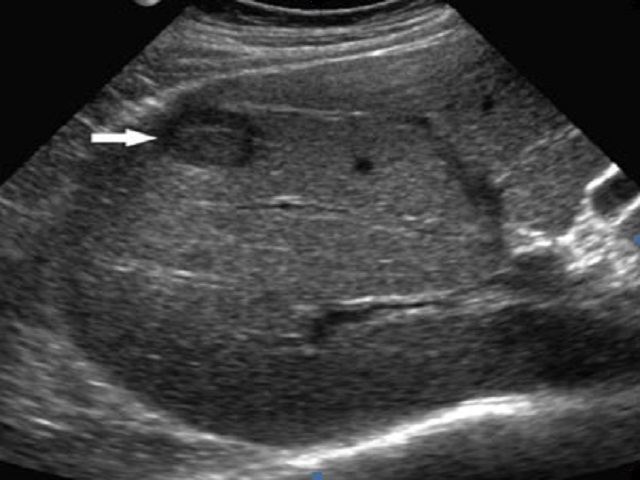

- УЗ исследование – в основе метода лежит отражение эхо-сигнала от тканей органа и построение его изображения.